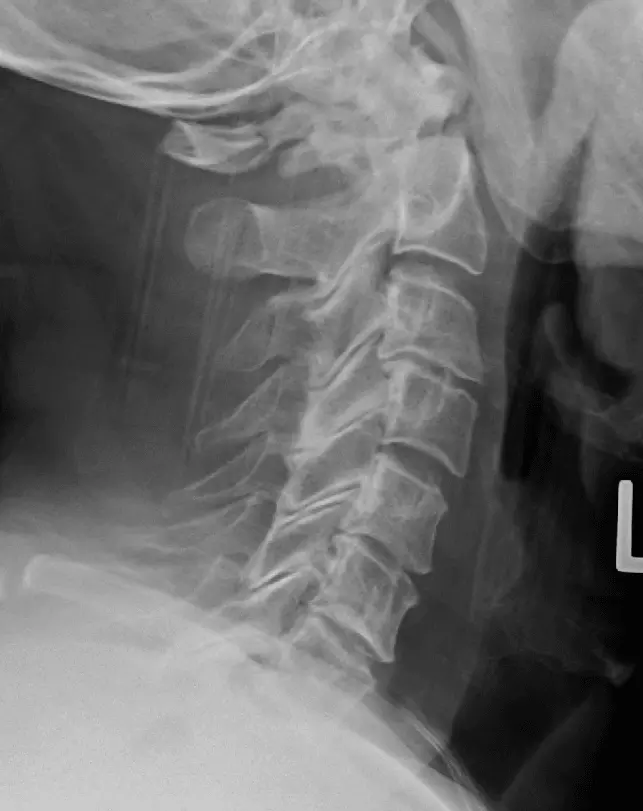

When imaging the C-spine, AP (anterior-posterior), lateral and ‘open mouth’ views are taken. A Jefferson fracture refers to a fracture of the atlas (C1). A Hangman’s fracture refers to a fracture through the pars interarticularis of C2. A fracture of the odontoid peg is best seen with an ‘open mouth’ view. For more information, check out our article on Conditions of the Back and Neck.

Image - Lateral radiograph of the C-spine showing a Jefferson’s fracture (C1)

Creative commons source by James Heilman, MD [CC BY-SA 4.0 (https://creativecommons.org/licenses/by-sa/4.0)]